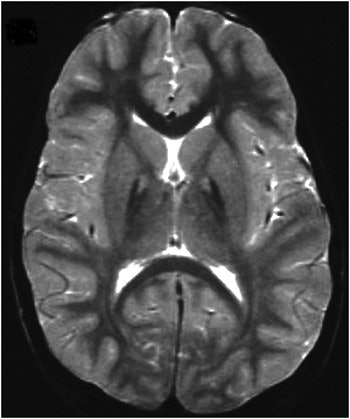

The patients underwent T2-weighted MRI. The results showed a specific pattern of hyperintensity within the hypointense medial globus pallidus. "Magnetic resonance imaging revealed the same brain disease patterns in each and every one of these patients," Hayflick said in an interview with AuntMinnie.com. "The strong correlation between specific MRI changes and the presence of a PANK2 mutation is very unusual in medicine, but there were no exceptions in this group of subjects."

| Patient with PANK2 mutation and eye of the tiger sign on MRI. Image courtesy of Dr. Susan Hayflick. |

On the basis of this correlation, the investigators assessed the value of MRI by itself as a predictor of mutation status. They identified a subgroup of patients with Hallervorden-Spatz syndrome whose clinical and radiographic data had not been originally included in the study. They found six patients with the presence of the eye of the tiger sign and analyzed their DNA for PANK2 mutations. All six patients were found to have PANK2 mutations on both chromosomes, supporting the correlation between the presence of these mutations and the eye of the tiger sign.

"Patients with the classic form of Hallervorden-Spatz syndrome should provisionally be given the diagnosis of pantothenate kinase-associated neurodegeneration, awaiting confirmation by DNA analysis," the investigators concluded. "Patients with atypical Hallervorden-Spatz syndrome who present with speech and psychiatric disorders and whose brain MRI scans have the eye of the tiger sign should undergo analysis for PANK2 mutations."